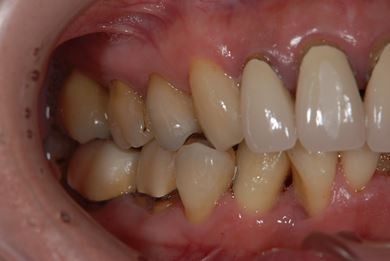

| 性別/年齢 | 女性 / 40歳 | ||||||||||||||||||||||||||||||||

| 主訴 | 前歯のつけ根の黒い部分を見えないようにしたい。 | ||||||||||||||||||||||||||||||||

| 治療方針 | 上顎前歯をセラミック治療にて審美的回復を行う。 | ||||||||||||||||||||||||||||||||

| 治療内容 | オールセラミッククラウン4本(セラミック用土台4本) | ||||||||||||||||||||||||||||||||